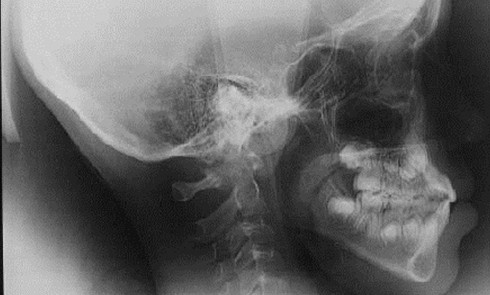

Article réservé à nos abonnés La bascule du plan d’occlusion

La bascule du plan d’occlusion est une anomalie pouvant être causée par des anomalies de posture ou des anomalies de...